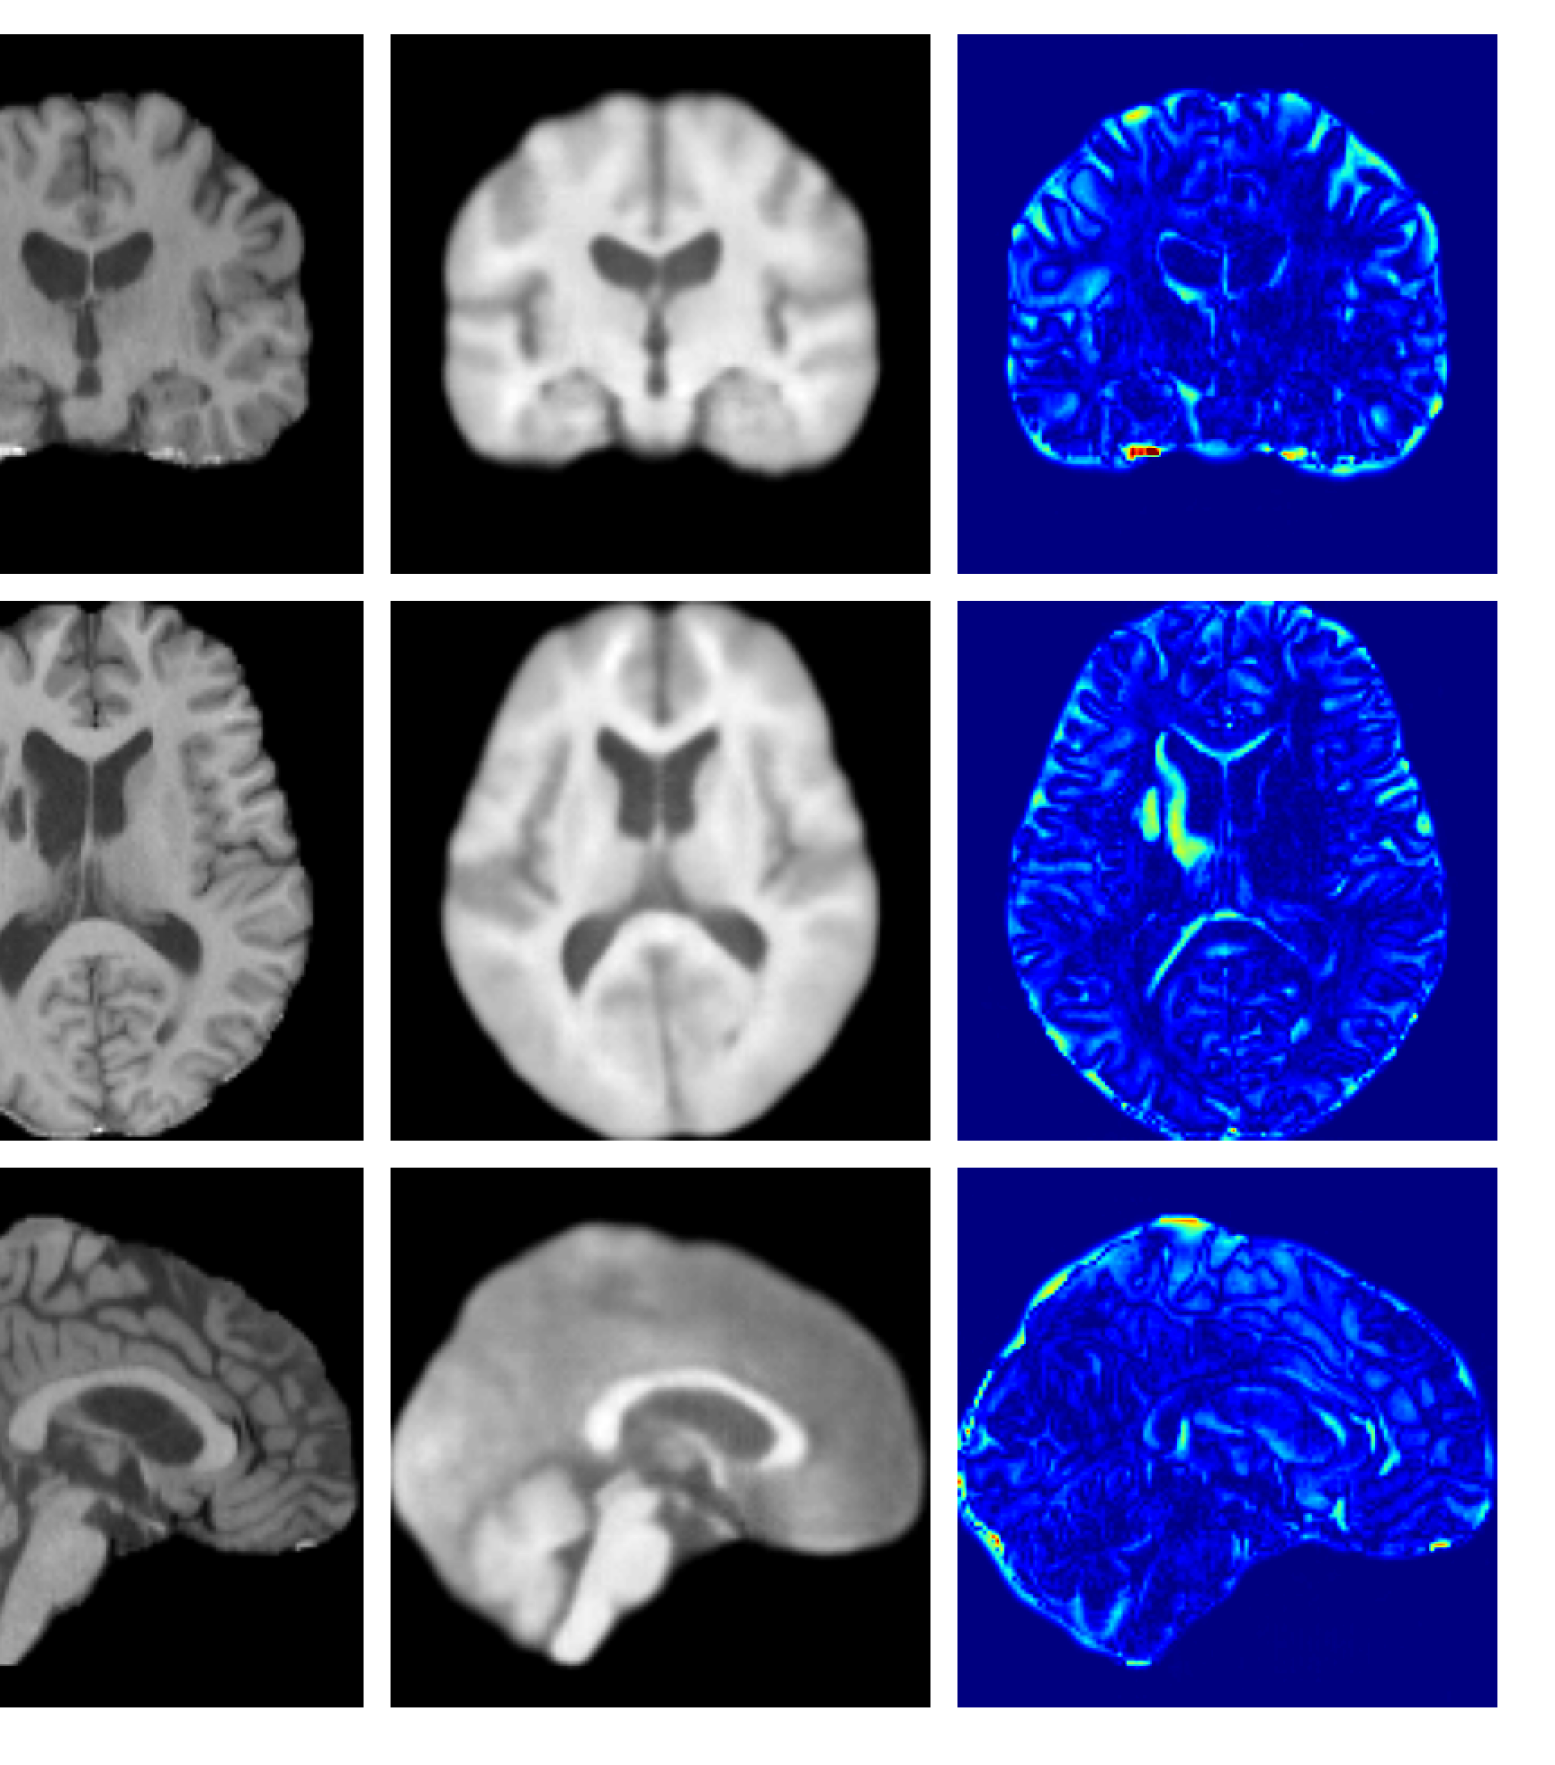

Figure 4: Example reconstructions and anomaly maps from a disease cohort sample in the UoTH dataset, shown for the top three models. The lesion is highlighted in red in the original image.

Figures 3 and 4, show example reconstructions and abnormality maps for a sample from the UKBB and UoTH datasets, respectively. Enlarged figures and additional example qualitative results for the ADNI dataset are available in the Supplementary. In Figure 3 we see that whilst all models are able to detect the lesion visible in the sagittal slice, the VAE, cVAE, LDM and LDM (TavgT_{avg}) produce very smooth outputs or lose defining characteristics and thus exhibit more false positives in healthy tissue. THOR and CADD provide the best results, with CADD better detecting white matter hypointensities (WMH). However, neither method fully inpaints all WMH, potentially due to presence of WMH in the healthy training set.

For the UoTH dataset, Table 2 shows that whilst CADD outperforms all other DDPM methods, it is outperformed by the VAE and cVAE models. Unlike the UKBB and ADNI datasets, the UoTH dataset contains noisy images with larger lesions and regions of pathology. Here, the CADD threshold, which limits the number of regions flagged as anomalous at each inpainting step, may be too stringent to fully inpaint extensive anomalies. It should be noted, however, that the improved disease detection performance of the VAE and cVAE models comes at the cost of accurate reconstruction of healthy tissue as illustrated in Table 1 and Figure 4. Such poor quality reconstructions would not be suitable for downstream tasks such as anomaly segmentation or image processing algorithms.

Figures 8 and 9 are enlarged versions of Figures 3 and 4 respectively, with the latter now including results from all compared methods. Figure 10 provides example reconstructions and anomaly maps for an AD subject from the ADNI disease cohort.

Refer to caption

Figure 9: Enlarged example reconstructions and anomaly maps for a sample from the disease cohort of the XXXH dataset. The lesion region is indicated in the original image by the red box.